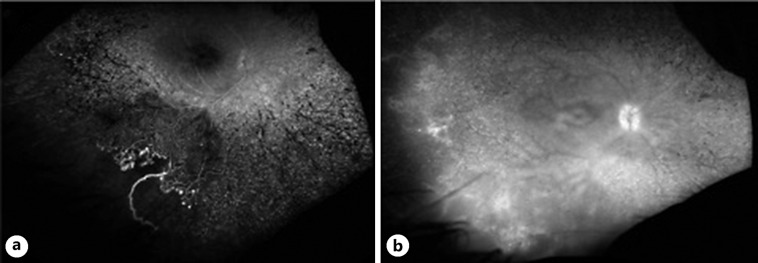

Case report: A 13-year-old female presented with pain in her left eye and no light perception in that eye. She was found to have left eye advanced neovascular glaucoma related to VPT in the context of MYO7A-related Usher syndrome. Intraocular pressure and pain were controlled with external diode cyclodestruction. Almost 3 years later, early asymptomatic VPT was noted in the right eye during follow-up and was treated with laser photocoagulation.